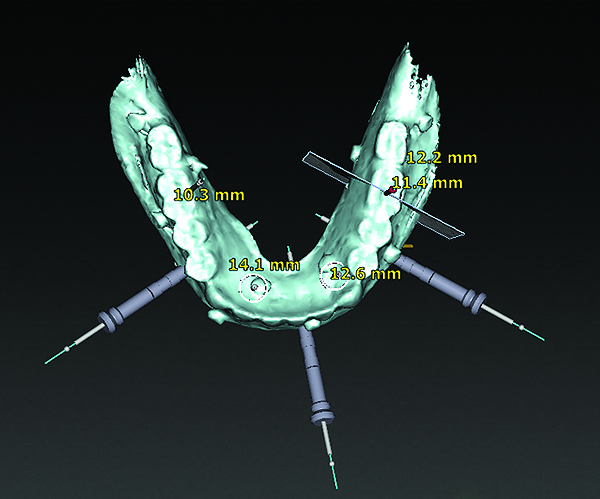

3D radiographic files (CT, CBCT) are stored digitally using a standardized digital imaging and communication in medicine (DICOM) format. In combination with a radiographic guide fabricated from a diagnostic wax-up, CBCT can be used to plan implant location and angulation based on prosthetically driven parameters and local bone/tissue constraints (Figure 8 through Figure 11). Currently, there are two different protocols to incorporate the radiographic guide in 3D scans and to perform computer guided surgery. The first is the double scan protocol, in which the patient wearing the radiographic guide and the radiographic guide alone are scanned separately. Fiduciary markers incorporated in the radiographic guide allow for matching of the two scans. This protocol allows for digitization of the surgical guide with great accuracy, irrespective of errors introduced by patient scans.18 Specialized software can be used to create a surgical guide (Figure 12).

(8) The use of CBCT and digital software for implant treatment planning. The radiographic guide in combination with a 3D CBCT was used to help plan implant position and location.

Figure 8

(9) The use of CBCT and digital software for implant treatment planning. The radiographic guide in combination with a 3D CBCT was used to help plan implant position and location.

Figure 9

(10) The use of CBCT and digital software for implant treatment planning. The radiographic guide in combination with a 3D CBCT was used to help plan implant position and location.

Figure 10

(11) The use of CBCT and digital software for implant treatment planning. The radiographic guide in combination with a 3D CBCT was used to help plan implant position and location.

Figure 11